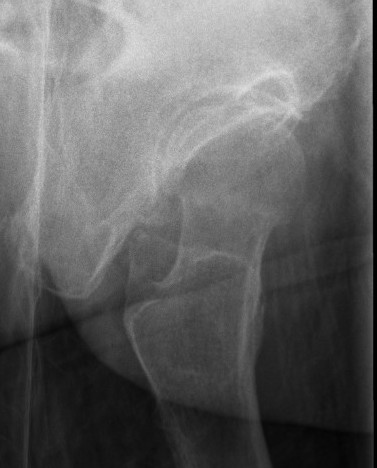

Type I: Incomplete, valgus impacted fracture

Type II: Complete fracture, undisplaced

Type III: Complete fracture, partial displaced, trabeculae don't line up with acetabulum

Type IV: Complete fracture, completely displaced, trabeculae line up with acetabulum

AVN

Increased with

- displaced fractures

- younger age

- female

- 1000 patients treated with fixation

- undisplaced: AVN 4%

- displaced: AVN 10%

- displaced: men 5%, women 11%

- displaced: < 60 20%, 60 - 80 13%, > 80 3%